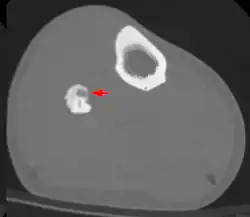

Diagnosis

Radiographs in osteoid osteoma typically show a round lucency, containing a dense sclerotic central nidus (the characteristic lesion in this kind of tumor) surrounded by sclerotic bone. The nidus is seldom larger than 1.5 cm.

The lesion can in most cases be detected on CT scan, bone scans and angiograms. Plain radiographs are not always diagnostic. MRI adds little to the CT findings which are useful for localisation. Radionuclide scanning shows intense uptake which is useful for localisation at surgery using a hand held detector, and for confirmation that the entire lesion has been removed.[8][9]